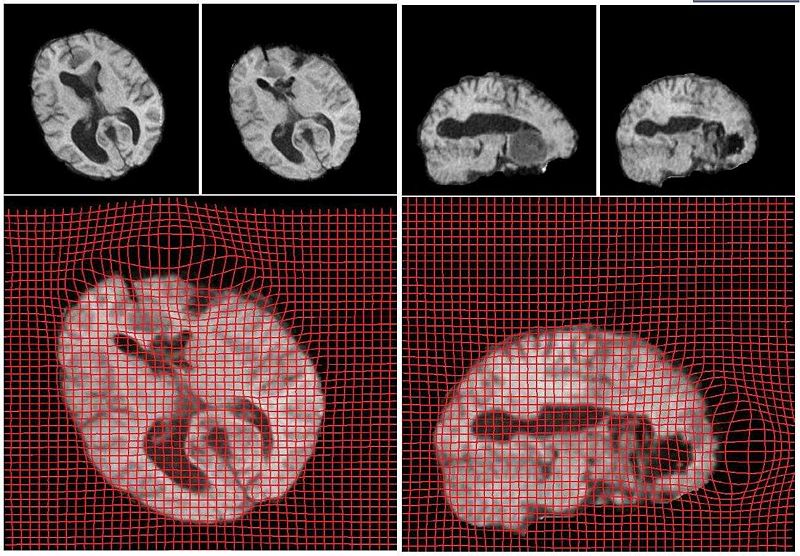

Below we show the results from registration of two 3D brain MRI datasets. The first data set was pre-operative while the second data set was acquired during surgery (craniotomy). Both were resampled to 256*256*256 for uniform voxel size and the skull was removed. We show the results on an axial and a coronal slice of the 3D brain volumes. The sag and compression areas can easily be seen in the deformed grid shown below. The reults shown are after 3600 iterations, requiring less than 15 minutes of computation time (Dual Xeon 1.6GHz + nVidia GeForce 8800 GX GPU. The optimal computation time was found to occur for a grid size of 128*128*128 where about 1000 iterations execute in less than 15 seconds. This is due to the memory limitations on the graphics card used. The results on an axial and coronal slice are shown below: